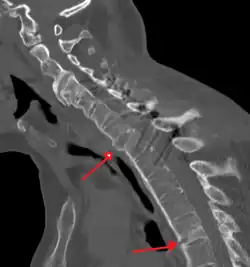

Fracture of the T5 and C7 vertebra due to trauma in a person with ankylosing spondylitis as seen on a CT scan

Prognosis is related to disease severity.[11] AS can range from mild to progressively debilitating and from medically controlled to refractory. Some cases may have times of active inflammation followed by times of remission resulting in minimal disability while others never have times of remission and have acute inflammation and pain, leading to significant disability.[11] As the disease progresses, it can cause the vertebrae and the lumbosacral joint to ossify, resulting in the fusion of the spine.[44] This places the spine in a vulnerable state because it becomes one bone, which causes it to lose its range of motion as well as putting it at risk for spinal fractures. This not only limits mobility but reduces the affected person's quality of life. Complete fusion of the spine can lead to a reduced range of motion and increased pain, as well as total joint destruction which could necessitate a joint replacement.[45]

Osteoporosis is common in ankylosing spondylitis, both from chronic systemic inflammation and decreased mobility resulting from AS. Over a long-term period, osteopenia or osteoporosis of the AP spine may occur, causing eventual compression fractures and a back "hump".[46] Hyperkyphosis from ankylosing spondylitis can also lead to impairment in mobility and balance, as well as impaired peripheral vision, which increases the risk of falls which can cause fracture of already-fragile vertebrae.[46] Typical signs of progressed AS are the visible formation of syndesmophytes on X-rays and abnormal bone outgrowths similar to osteophytes affecting the spine. In compression fractures of the vertebrae, paresthesia is a complication due to the inflammation of the tissue surrounding nerves.